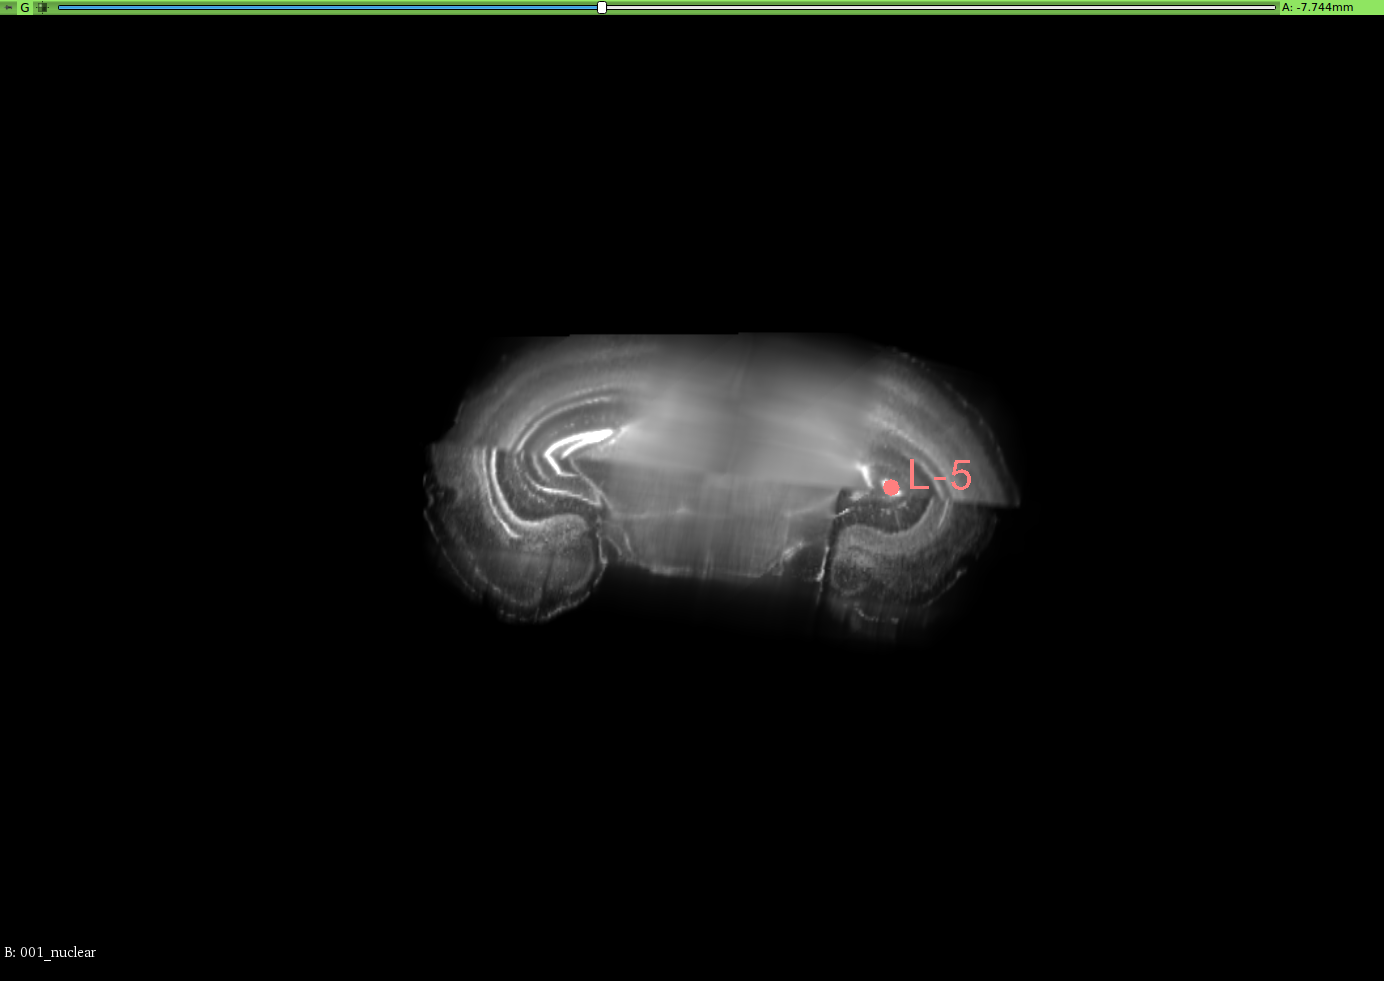

To validate the registration performance of the proposed methods and comparing the baseline methods in a more objective manner, a landmark registration test is conducted. In the CUBIC dataset, three brains are used to test the registration performance. In the landmark test, the same dataset is used for the performance validation. 12 landmarks are selected and all of these landmarks are selected where their positions vary in all three axis. 3D slicer tool is used to select the landmarks for this experiment from the CUBIC brains. A set of selected landmarks are shown in Figure 7. Table 3 shows the results of the 3D landmark registration by proposed InvGAN method and other baseline methods. The Euclidean distance between the registered landmarks and reference landmarks are presented in mm. For optimisation-based ANTS and Elastix tools, the same parameter sets are used to register landmarks selected from moving image and fixed image. After the registration, the output point locations are compared with reference point locations in the fixed image. For the deep-learning-based VoxelMorph and InvGAN, the deformation values in X,Y and Z are extracted from the same voxel location of the selected landmark’s voxel location. After applying deformation to the landmarks, the new position is compared with that of corresponding reference points in the fixed image.

Refer to caption

(a) Brain-1

(b) Segittal View

(c) Coronal View

(d) Corresponding Points in Brain003

(e) Segittal View

(f) Coronal View

(g) Brain-2

(h) Segittal View

(i) Coronal View

(j) Corresponding Points in Brain-3

(k) Segittal View

(l) Coronal View

Figure 7: 3D Landmarks